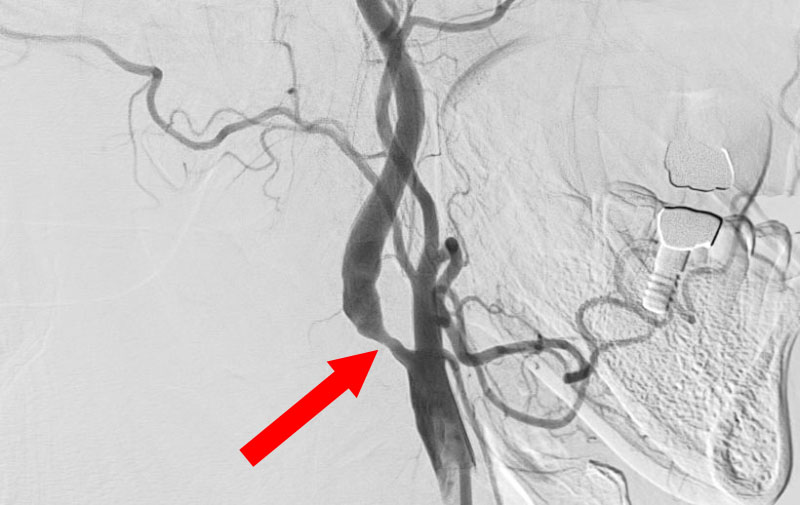

'25年7月

左内頚動脈狭窄症

70代

大阪府の病院

No.1561 手術前

No.1561 手術中

No.1561 手術後